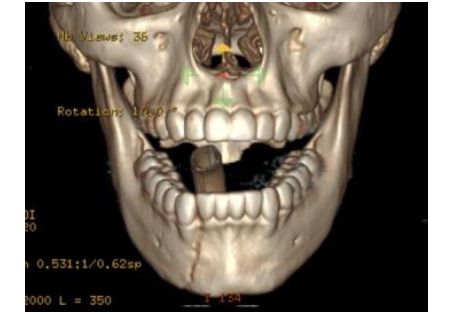

A 27-year-old man is admitted to the emergency department after being injured in an altercation. Physical examination shows objective malocclusion with a left-sided crossbite and right-sided open bite. A CT scan is shown. Which of the following muscles is most likely responsible for these radiographic and physical examination findings?

The correct response is Option B.

The patient described has typical radiographic and physical exam findings of a right subcondylar mandibular fracture. Anteromedial displacement of the condylar segment out of the glenoid fossa occurs secondary to pull from the lateral pterygoid muscle, which normally functions in anterior translation of the condyle across the articular eminence of the temporal bone during wide mouth opening. This leads to loss of height of the mandibular ramus and a premature occlusion on the fracture side. This causes the typical findings of condylar/subcondylar fractures: ipsilateral crossbite and contralateral open bite. The masseter and medial pterygoid form the pterygomasseteric sling, which attaches from the skull base and zygoma to the inferior mandibular border, and is responsible for fracture displacement after angle and body fractures. The mylohyoid and genioglossus muscles run along the floor of the mouth and can contribute to fracture displacement in the body and parasymphyseal region.